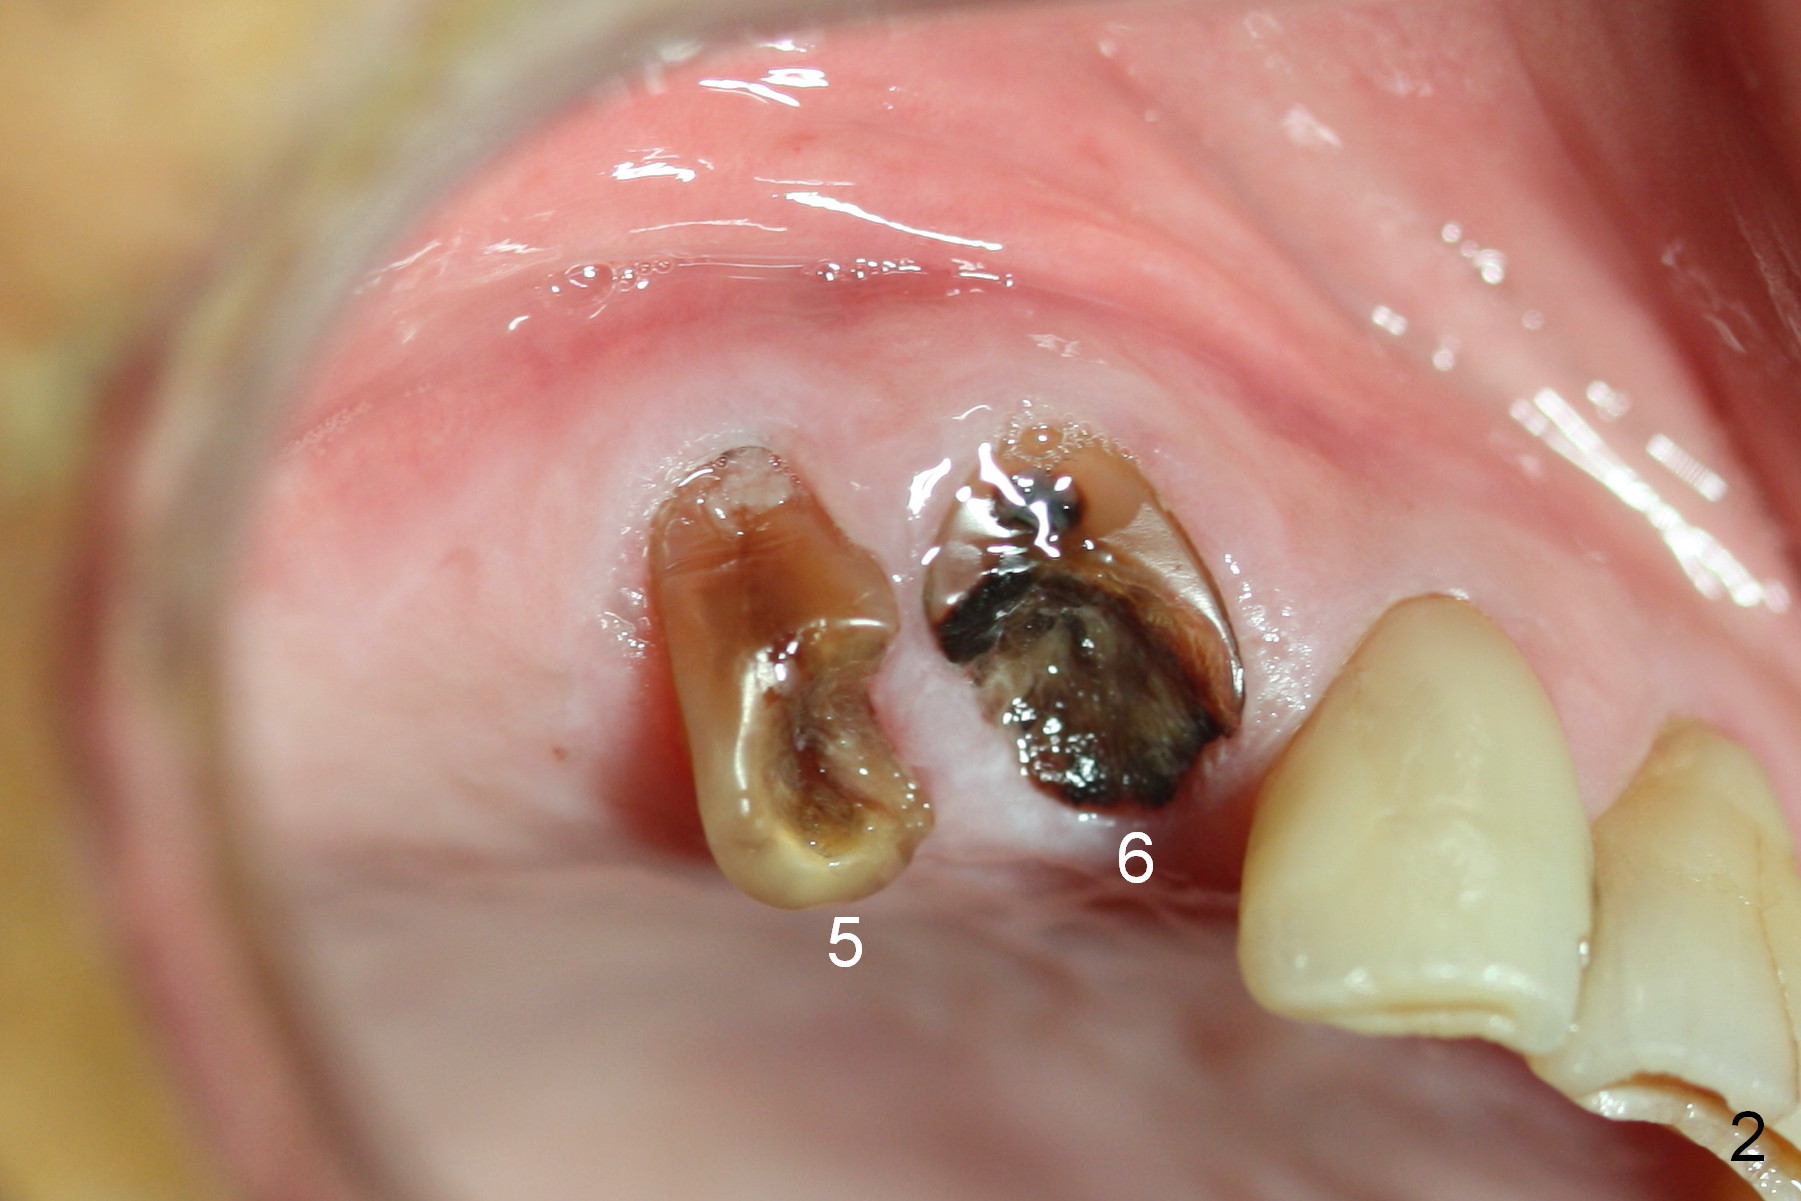

Several of CK's upper teeth (apparently in cross bite) are to be restored with implants (Fig.1). The first two are #5 and 6; note the oval roots (Fig.2). After extraction, and curettage, osteotomy starts in the palatal aspect of each socket. The 1st intraop PA shows that the trajectory at #6 is incorrect (Fig.3). After adjustment, osteotomies look parallel (Fig.4: D: 3.5x20 mm drill; T: 4.5x20 mm tap). This suggests how important it is to use parallel pins to check initial osteotomies for neighboring implants (Fig.3). The trajectory of the implants remains acceptable (Fig.5: 4.5x20 mm with insertion torque »60 Ncm); so is the position of the implants (as palatal as possible; Fig.6 (*: bone graft)). Immediate provisionals are fabricated in cross bite.